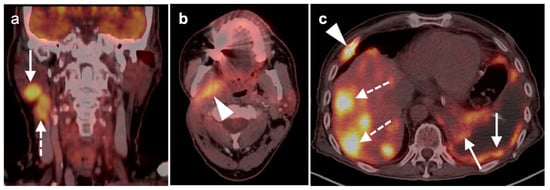

2.6. Thyroid Cancer